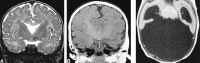

<sc>fig</sc> 4.

fig 4.

Spatial orientation of the thalami. A, Grade 0: Axial T2-weighted image shows the thalami with their long axes at an angle approximately 30° to 45° relative to the plane of the IHF (arrows). B, Grade 1: Axial T2-weighted image shows the thalami with their long axes approximately parallel to the plane of the IHF (arrows). C, Grade 2: Axial T2-weighted image shows the thalami with their long axes approximately perpendicular to the plane of the IHF (arrows).